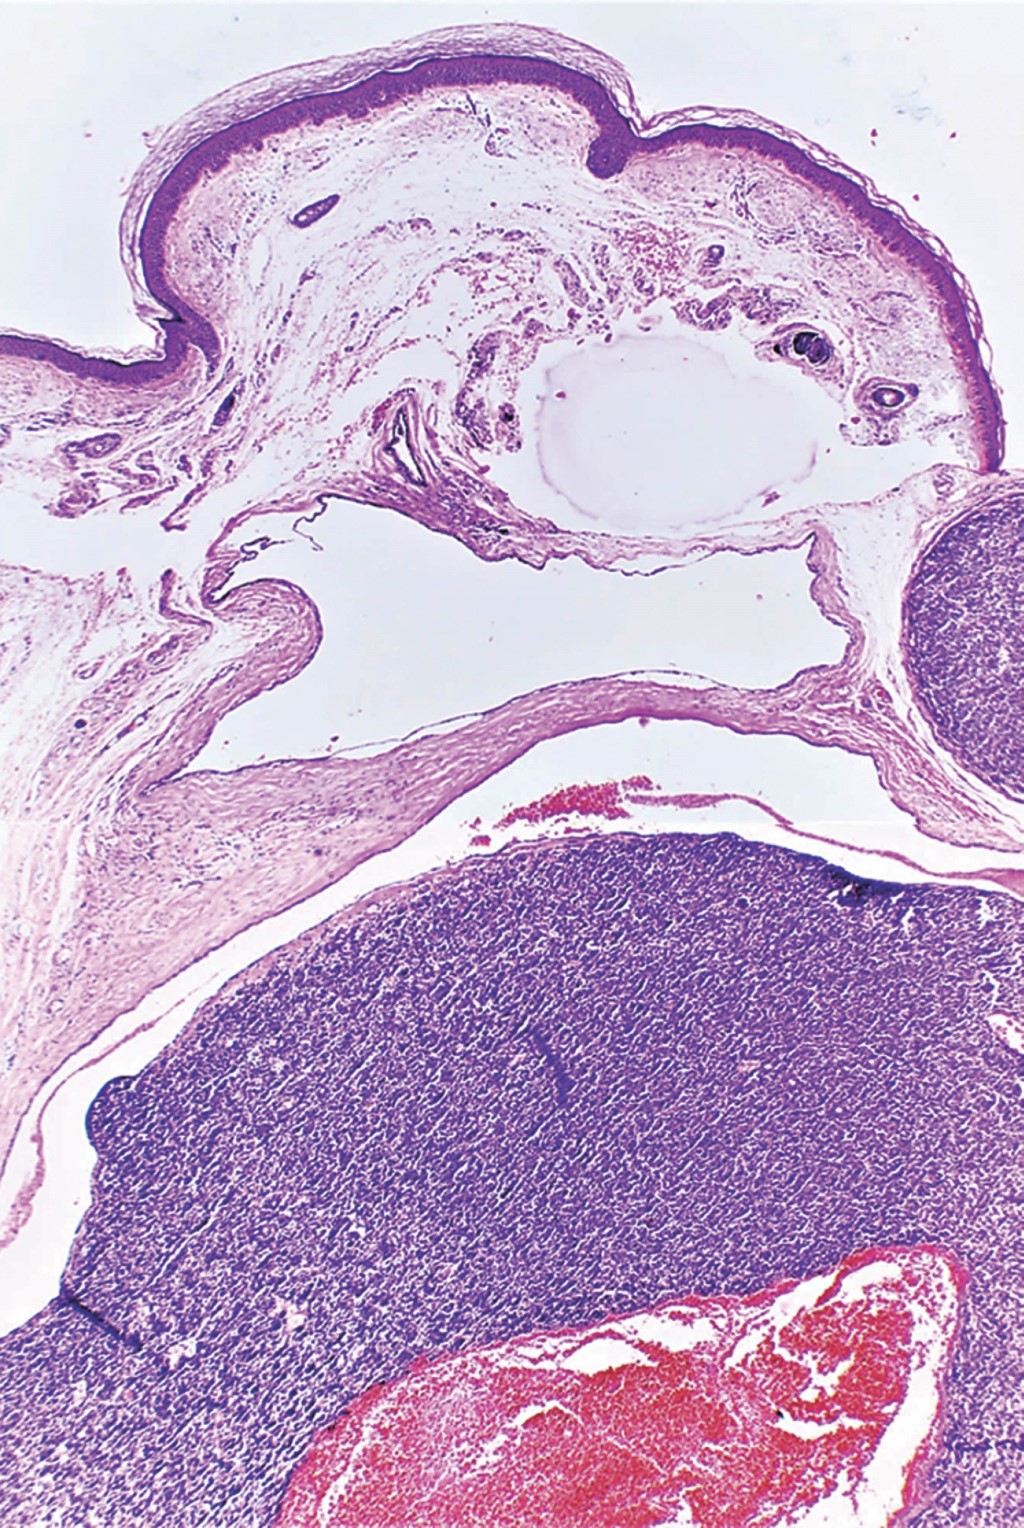

Figure 1